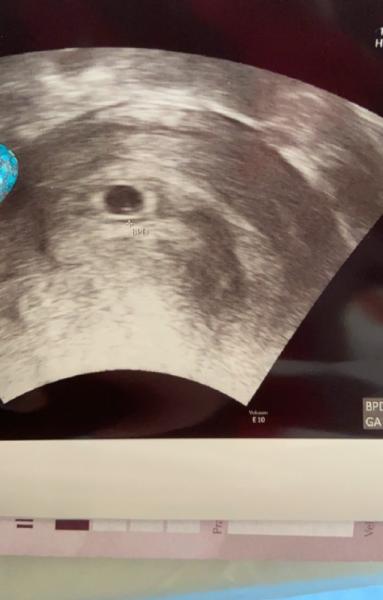

Hey sieht ja fast wie meins aus und weiß noch nicht ganz welche Woche außer das Periode Rechnung nicht hinhaut

Bild zu